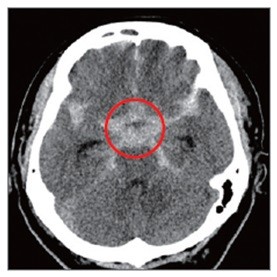

뇌동맥류로 인해 부풀어 오른 혈관이 터지면 뇌출혈이 생긴다. 이 경우 사망 위험이 크게 증가하고 뇌에 영구적 손상이 가해져 언어장애, 운동장애 등이 유발된다.

뇌동맥류를 파열 전 발견해 치료하면 95% 이상에서 좋은 결과가 나타난다. 치료는 주로 ‘클립결찰술’과 코일색전술’로 이뤄진다. 클립결찰술은 이마 부위 두개골을 열고 클립 같은 고정 핀으로 부풀어 오른 뇌동맥류를 졸라매는 수술법이다. 코일색전술은 머리를 절개하지 않고 사타구니에 있는 대퇴동맥을 통해 뇌동맥에 가느다란 도관을 넣은 뒤 뇌동맥류 내부를 백금 등으로 만들어진 특수 코일로 채워 막는 방식이다. 뇌수술이 어렵거나 직접수술이 위험성이 큰 환자에게 적합하다.